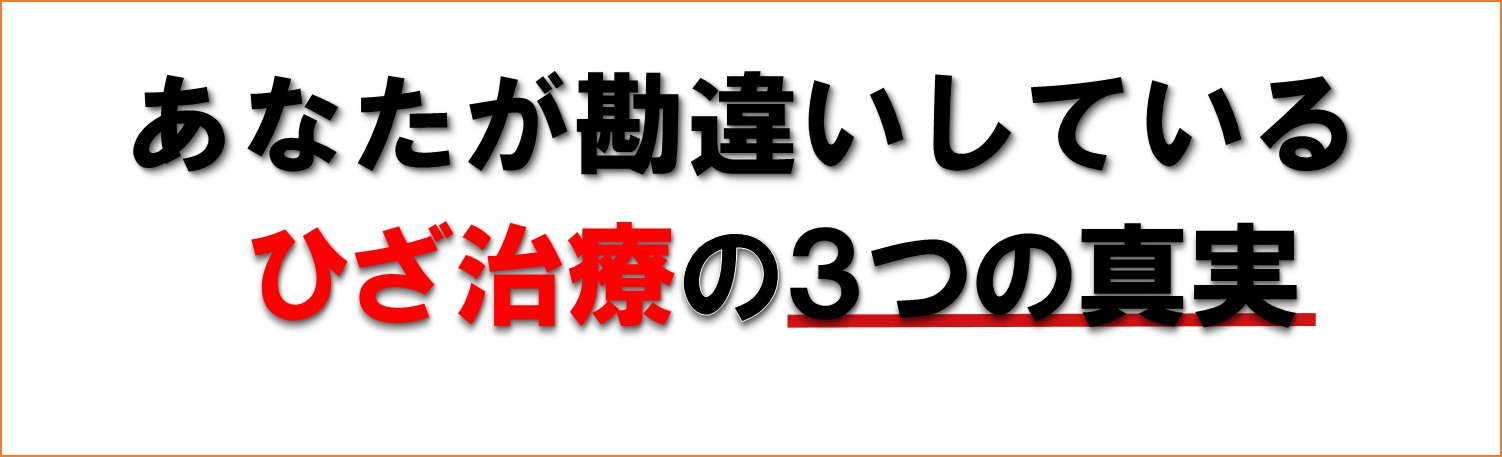

���̇@�@�ɂ������}�b�T�[�W����Ηǂ��Ƃ����Ԉ�����^��

�͂����������ƃ}�b�T�[�W�͒ɂ݂ɑ����t�����ł��B

�m���Ƀ}�b�T�[�W�͋C�������ł����ʂ����ċC�������̂����ÂƂ�����ł��傤���H

�����P�ɁA�G���ɂ���ΕG����𝆂ށA�����肪����Ό����ق����B

���̏ꂻ�̏�̑Ώ������Ŗ{���ɗǂ��Ȃ�̂ł��傤���H���Ȃ��͗ǂ��Ȃ�܂������H

������NO�ł��B�����獡�A���@�̃y�[�W�����Ă���͂��ł��B

����͎��Âł͂Ȃ��C�����������̖����ł��I

�����ؓ��𝆂݉߂��邱�Ƃŋt�ɋؓ��������Ă��܂��A�]�v�ɃR���ł܂�ɂ݂��N����܂��B�ɂ݂��悭�Ȃ�܂��B���ݕԂ����N���邱�Ƃ�����܂��I

���̌��ʃ}�b�T�[�W�ł̓��~�Ԃ��Ƃ����Đg�̂�����ǂ��Ȃ��Ă��܂�����A�ǂ�ǂ��h���łȂ��Ɩ����ł��Ȃ��g�̂ɂȂ��Ă��܂��܂��B

���̇A�@�ɂݎ~�߂⒍�˂��ŗǂ��Ȃ�Ȃ��^���ɂݎ~�߂⒍�˂��ꎞ���̂��̕��@�ł��B

�a�@�œ�����O�̂悤�ɂ����Ȃ��Ă��鏈�u�ł����{���ɂ���Ŏ���̂ł��傤���H

�m���ɒɂ݂��������ɒɂ݂�}���鎖�͕K�v�ł��B�ł����A������������g�p����̂͂ǂ����Ǝv���܂��B

��{�I�ɁA��͎������߂̂��̂ł͂���܂���B���̏�̒ɂ݂�}���邽�߂̂��̂ł��B�ꎞ�I�ȏ��u�ɂ����܂���B��͓łł��B

�ɂ݂�}���Ă���ԂɁA�g�̂̂����Ă��鎩�R�����͂��g���ĉ����Ă����͂��Ȃ̂ł����A���������ɂ݂͏o�Ă��鎞�͎����͂���������ł���̂ŁA���Ă����܂���B��ł͖�����Ɠ����Ŋ��o��݂����Ă邾���ł��B

����ɋC�t�����ɖ�t���ɂȂ�ƒɂ݂�}������Ȃ��Ȃ�̂ł����ӂ��B

���̇B�܂��͉摜�ɂ�錟�������i�����g�Q����MRI�Ȃǁj �摜�����ł��G�ɂ̌����͂킩��܂���B

������������܂��A���E�I�ɂЂ��ɂʼn摜�����͍s���Ȃ��Ȃ��Ă��Ă��܂��B���R�͖��m�ŁA�摜�łЂ��ɂ̌����͂킩��Ȃ�����B

�ߋ����E�ό`������B�ł��ɂ݂̖����l�͎R�قǑ��݂��܂��B

�����̂��Ƃ���A�摜�ɂ��ɂ݂̌����̐����͖������܂��B

�t�Ɂu����͂Ђǂ��ό`���I����Ԃ�Ă�I�v�Ȃǂƌ����āA�s����|���ɂ��X�g���X�Œɂ݂���������P�[�X�����X����܂��B

����ȊԈ�����펯�ɘf�킳��Ȃ��ʼn������ˁB